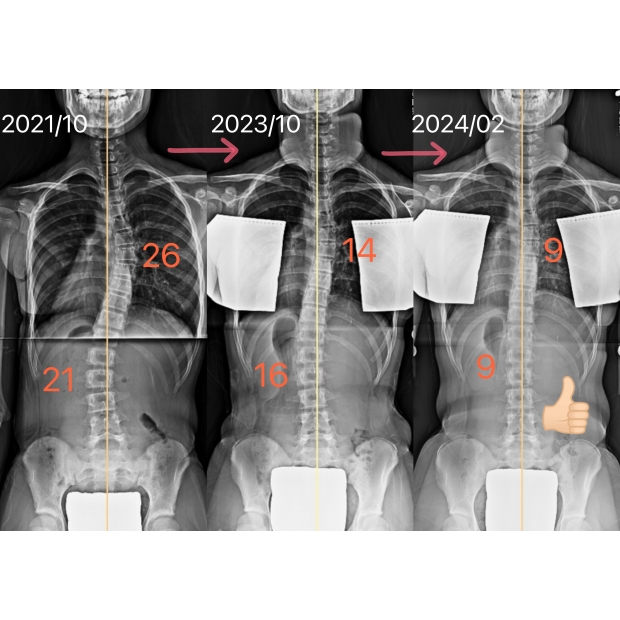

12歲國一女生胸彎26度,矯治4個月,度數改善至9度,幾乎直了

女孩胸彎26度,旋轉14度,矯治4個月後追蹤胸彎只剩9度,進步了65%!

旋轉降至5度,右背部的凸起明顯降低了,體態也更好看了